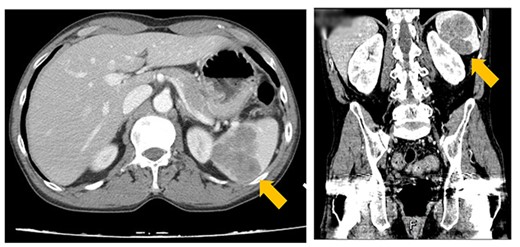

A 49-year-old man with a history of myasthenia gravis and malignant thymoma had undergone radiotherapy and an extensive thymectomy in 2011. However, 2 years later, an abnormality was detected on a chest computed tomography (CT) scan, a suspicion of recurrent thymoma. Surgical resection at that time revealed only fibrosis according to the pathology report. An outpatient follow-up within 2 years after surgery revealed an increase in the patient’s acetylcholine receptor antibody levels from 79.5 to 107.12 nmole/L. In December 2021, follow-up CT scan (Fig. 1) revealed a lobulated, less enhanced mass measuring 5.8 × 5.3 cm in the patient’s spleen, along with mixed osteoblastic and osteolytic lesions in the L1 and L3 vertebral bodies. These findings prompted the suspicion of spleen and bone metastasis. Therefore, the patient was referred to our general surgeon and underwent splenectomy in January 2022.

CT image showing a lobulated, less-enhanced mass measuring 5.8 × 5.3 cm in the patient’s spleen, prompting the suspicion of splenic metastasis.